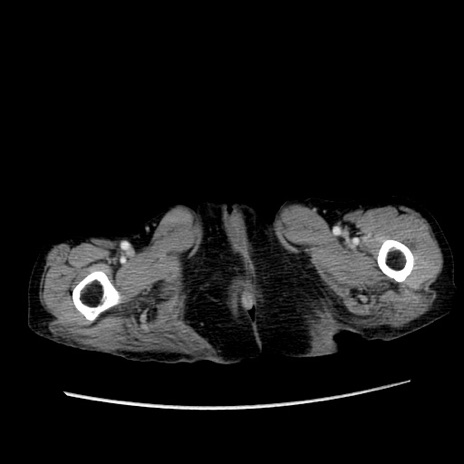

症例25(横断像)

症例

【症例】80歳代女性

【主訴】胸のつかえ感

【現病歴】約9時間前に食後から胸のつかえた感じあり、嘔吐あり、来院。

【既往歴】胃癌(全摘)、胆摘、虫垂炎

【身体所見】心窩部に圧痛あり、反跳痛なし。

【データ】WBC 5700、CRP 0.05